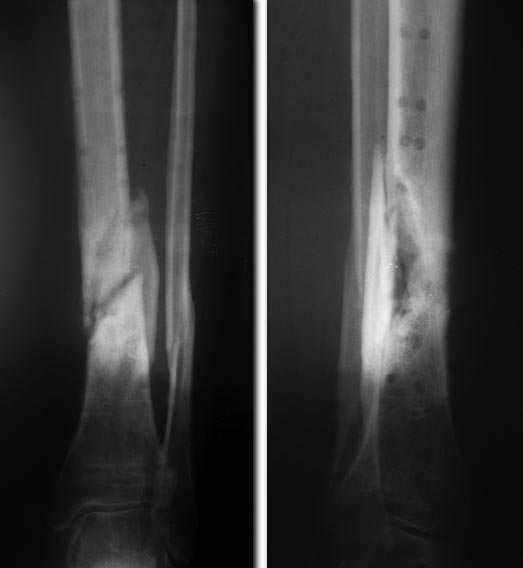

Спасибо,наглядно. Коллеги поделитесь,возможно сделать подобное шприцем Жане и можно в нем же замешать все компоненты сразу? какой цемент в данном случае лучше? Bvttncz СEMFIX1. Добавляю снимки пациентки. Понимаю, в рамках созданной темы это уже другой вопрос, но выскажите мнение по поводу установки такого гвоздя в данном случае. Свищи почти закрылись на фоне местного лечения. Гвоздь хотим поставить на фоне резко негативного отношения пациентки к АВФ